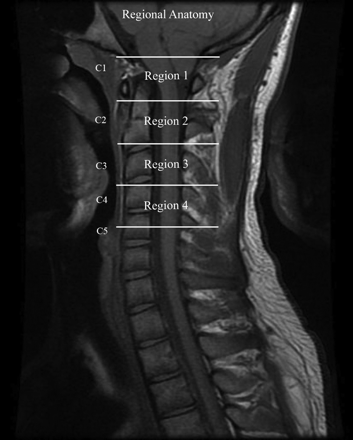

The cervical spinal canal was divided into 4 regions to encompass the anatomic locations of the sections obtained (Fig 1 ). Region 1 included the foramen magnum and upper C2; region 2, the mid C2 to the C2-C3 disk; region 3, the body of C3 to the C3-C4 disk; and region 4, the body of C4. One investigator (S.S.) then reviewed each flow study and assigned sections to each of the 4 regions.

The 4 regions in which CSF flow was measured in this study are designated by lines placed on an MR image of the lower foramen magnum and the cervical spinal canal.